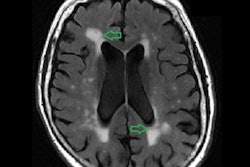

PET images show brain activity in a premenopausal woman (left) and in a postmenopausal woman (right). Brighter colors indicate higher metabolism, while darker colors indicate lower metabolism. The postmenopausal scan appears greener and darker, which means the woman's brain has substantially lower activity (more than 30% less) than the one to the left (no signs of menopause). Images courtesy of Weill Cornell Medicine.Women who had undergone menopause or were perimenopausal had markedly lower levels of glucose metabolism in several key brain regions than women who had not yet experienced menopause, the researchers found.